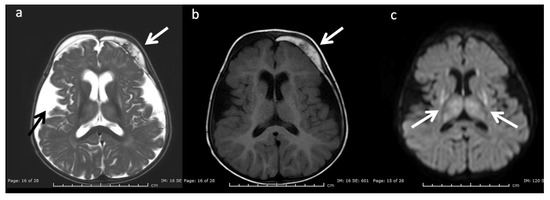

Figure 10.

Eleven-month-old female with Glutaric aciduria Type I with acute decompensation after illness. (a) Axial T2WI, (b) T1WI, and (c) DWI at the level of the basal ganglia demonstrate diffuse cerebral volume loss, underopercularization (black arrow, a), bifrontal chronic subdural hemorrhages with superimposed subacute left frontal subdural blood products (white arrows, a and b), and reduced diffusion in the lentiform nuclei and thalami (white arrows, c).

Glutaric Aciduria Type 1 (GA-I) (Figure 10): GA-I is a disorder of lysine, hydroxylysine, and tryptophan catabolism that results in characteristic MRI findings of poorly formed operculum, widened Sylvian fissures and frontotemporal CSF spaces, large cavum septi pellucidi, and basal ganglia lesions [3,7,8]. Supratentorial subdural hematomas may develop over time as a consequence of cerebral atrophy [20,36]. GA-I should be distinguished from glutaric aciduria type II that is caused by the inability to breakdown proteins and fats for energy and may present with underdeveloped frontotemporal lobes and enlarged sylvian fissures, delayed myelination, and hypoplasia of the corpus callosum [37].